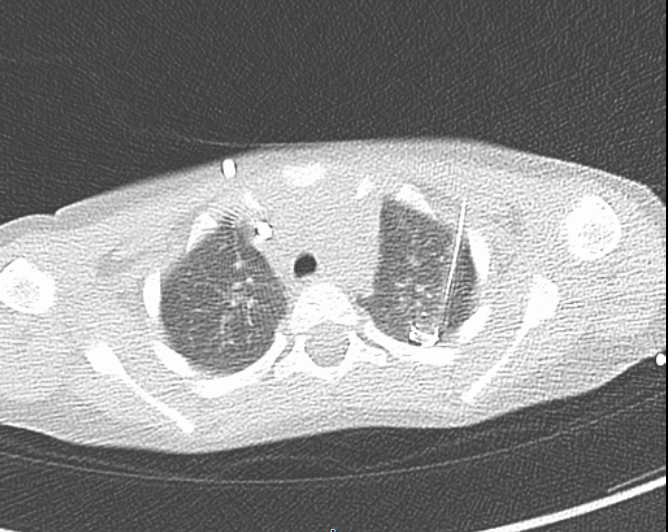

Lungenrundherde

Unklare Rundherde (Knoten) können auch an der kindlichen Lunge auftreten. Sie sind typischerweise asymptomatisch und werden meist durch eine Computertomographie (CT) im Rahmen einer anderen (Tumor-)Erkrankung auffällig. Im Kindesalter sind sie in der Bildgebung jedoch schwieriger einzuschätzen, sodass eine Gewebeentnahme (Biopsie) zur exakten Diagnostik oft nötig ist.

Diagnostik- und Therapiekonzept

Diese Biopsie wird in unserem Haus in der Regel thorakoskopisch, also minimalinvasiv, vorgenommen. Über kleine Hautschnitte wird eine Kamera in den Brustkorb eingeführt. Die in der CT gesehenen Knoten werden im Ganzen mit einem linearen Klammernahtgerät (Stapler) ausgeschnitten. Das Gewebe wird dann über einen Beutel aus dem Brustkorb geborgen und feingeweblich untersucht.

Kleine Lungenknoten und die, die nicht nahe der Lungenoberfläche lokalisiert sind, stellen thorakoskopisch häufig eine operative Herausforderung dar. Die Sichtbarkeit dieser Knoten ist oft kaum oder nicht gegeben, sodass wir für die Thorakoskopie Hilfsmittel benötigen. Daher sollte bei einem Pleuraabstand >5mm oder eine Größe unter 10mm eine präoperative Markierung erfolgen. Nach vorangegangenen Entzündungen, Operationen oder in schlecht einsehbare Lungenregionen kann diese Markierung auch sinnvoll sein.

Hierfür wird in Narkose direkt vor der Operation unter CT-Kontrolle ein Draht hinter den Lungenknoten geschoben. In der Operation kann dieser Draht dann verfolgt und der Knoten so identifiziert und herzusgeschnitten werden. Abschließend wird meistens eine Thoraxdrainage eingelegt, um eine regelrechte Entfaltung der Lunge zu gewährleisten.